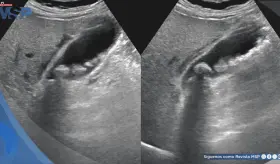

Un crecimiento preocupante en la incidencia de cánceres gastrointestinales, especialmente entre adultos menores de 50 años, ha encendido las alertas en la comunidad médica global.

Los investigadores descubrieron que, a los 60 años, casi el 10 % del revestimiento del estómago presenta mutaciones en genes asociados al cáncer.

Comprender estos factores de riesgo y adoptar medidas preventivas puede reducir las probabilidades de desarrollar esta enfermedad. La detección temprana, a través de exámenes regulares, es clave para mejorar los resultados y salvar vidas.

Reconocer los síntomas clave, como dolor abdominal, diarrea, sangrado rectal y anemia por deficiencia de hierro, puede marcar la diferencia en la detección temprana y el tratamiento efectivo de esta enfermedad.